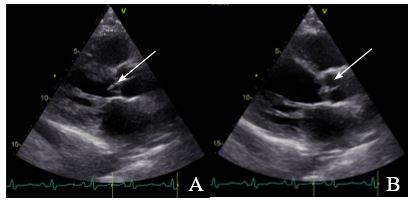

Subsequently, a second blood culture was obtained, indicating persistent bacteremia. A fecal occult blood test was performed to rule out colon cancer, but the result was negative. Serology tests for HIV and hepatitis B surface antigen (Table 2) were conducted to rule out immunodeficiency, and the results were also negative. In addition, a transthoracic echocardiogram (TTE) was performed, which revealed aortic valve vegetation measuring 1.4 cm × 0.4 cm, mitral valve stenosis secondary to valve sclerosis-consistent with the patient’s age-and dilated cardiomyopathy of valvular origin (Figure 2). As part of the presurgical evaluation, a coronary computed tomography angiography was also requested; however, despite the administered doses of beta-blocker, the scan could not be completed due to the absence of adequate negative chronotropic control. Consequently, a coronary arteriography with right and left heart catheterization was performed, with moderate pulmonary hypertension being the only positive finding.

Figure 2. Transthoracic echocardiogram showing vegetation on the native aortic valve. A) and B) Closed aortic valve.